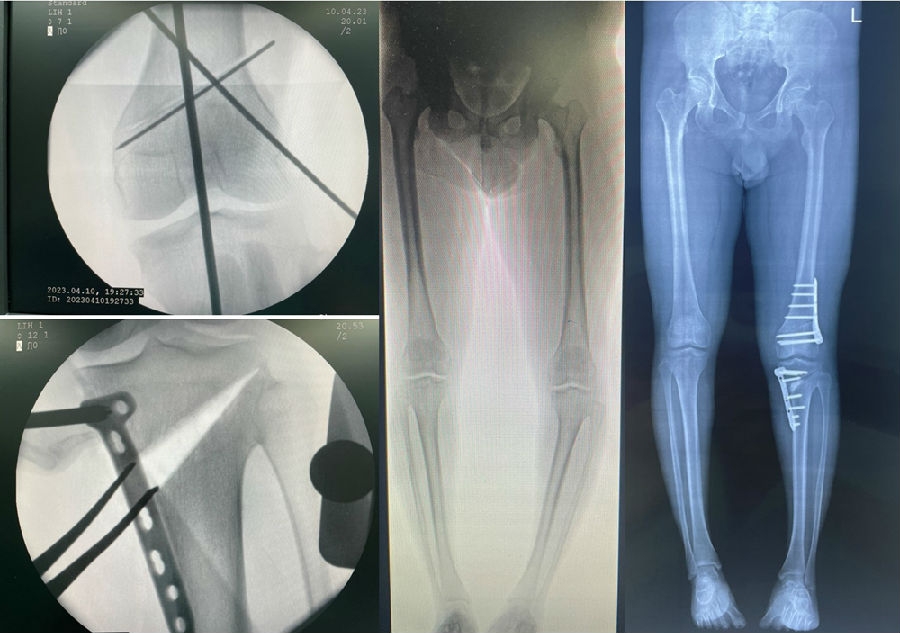

术后影像

患者二,女性,膝外翻,膝外侧疼痛。通过做畸形分析后发现,该患者同时存在股骨侧畸形、胫骨侧畸形和关节内畸形(LDFA=82°,MPTA=104°,JLCA=6°)。

对于这类病人如何进行术前设计的关键点就在于目标力线应如何设计。要在骨性截骨的时候纠正骨性畸形,关节内畸形要通过关节内的方法解决。因为JLCA不平行,所以要同时画股骨侧关节线和胫骨侧关节线,并垂直于股骨侧关节线做出股骨侧目标力线,垂直于胫骨侧关节线做出胫骨侧目标力线。

根据各自目标力线,分别计算股骨内侧闭合和胫骨内侧闭合角度。

此患者股骨内侧闭合6°,经股内侧闭合13°。

经典病例